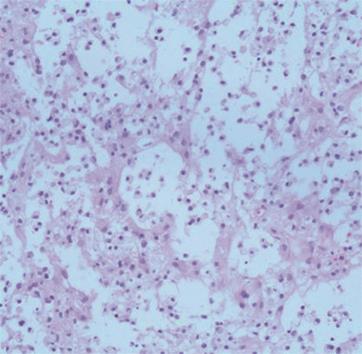

• 肿瘤样脱髓鞘病变报道3例

2023, 48(5):614-617. DOI: 10.13406/j.cnki.cyxb.003183

摘要 (95) HTML (24) PDF 1.29 M (241) 评论 (0) 收藏

摘要: